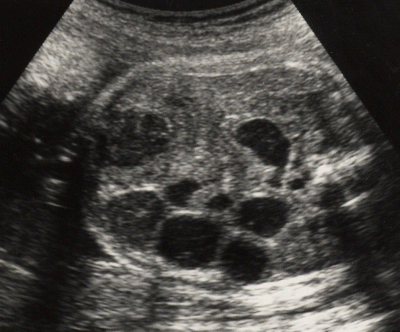

Qu’est ce que c’est?

polykystose rénale